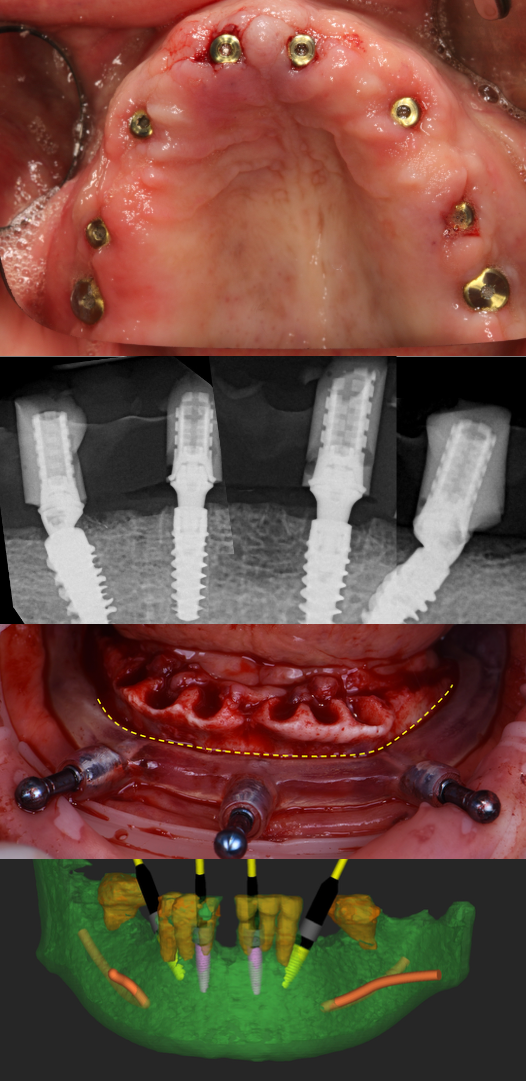

In this live webinar, Dr. Ziv Simon will break down full-arch implant treatment into a clear, repeatable formula. You’ll learn how to approach these cases with accuracy, confidence, and predictability—reducing stress, avoiding costly mistakes, and delivering life-changing results for your patients.

This is a practical, case-based session focused on how to think through full-arch cases step by stepnot theory.

• How to approach flapless full-arch surgery

• How and when to use stackable guides